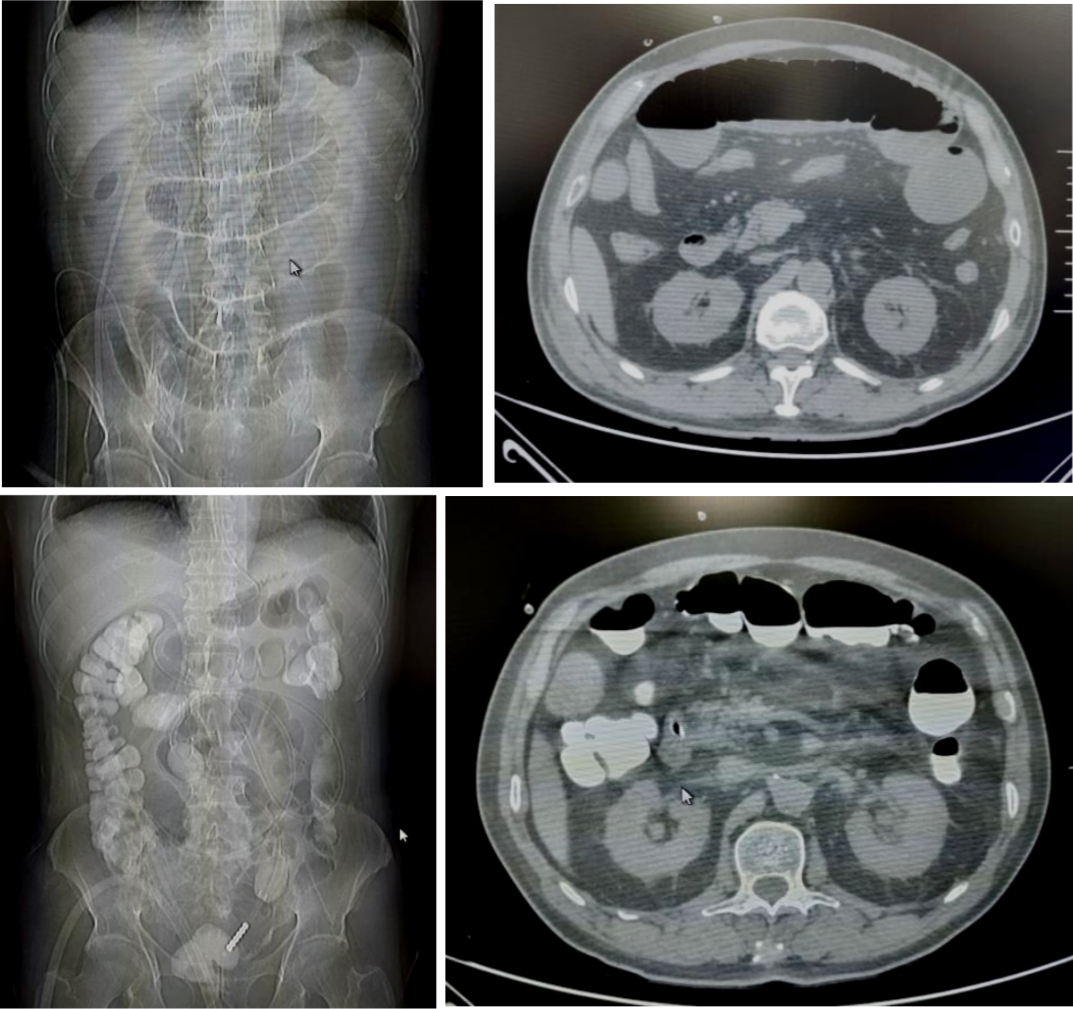

病例1

71岁的患者刘先生,因行膀胱癌根治术、回肠代膀胱术出现肠梗阻。后在我院放射介入室行DSA引导下经鼻肠梗阻导管置入术,术后当日患者腹胀较前明显缓解,术后第6天患者排气、排便,肠管恢复通畅,拔除肠梗阻导管。